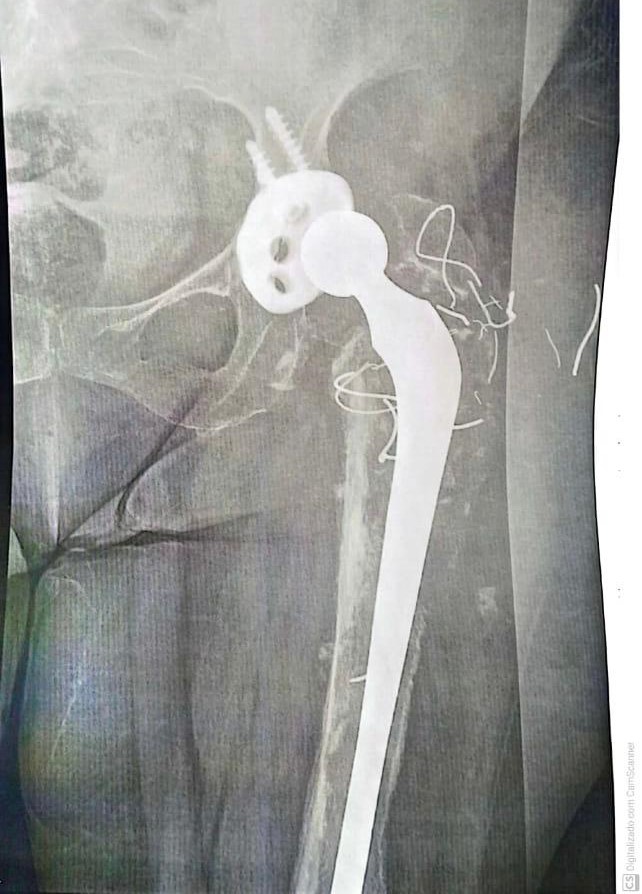

• Próteses de Quadril (Primárias  e Revisões);

• Cirurgia do Quadril;